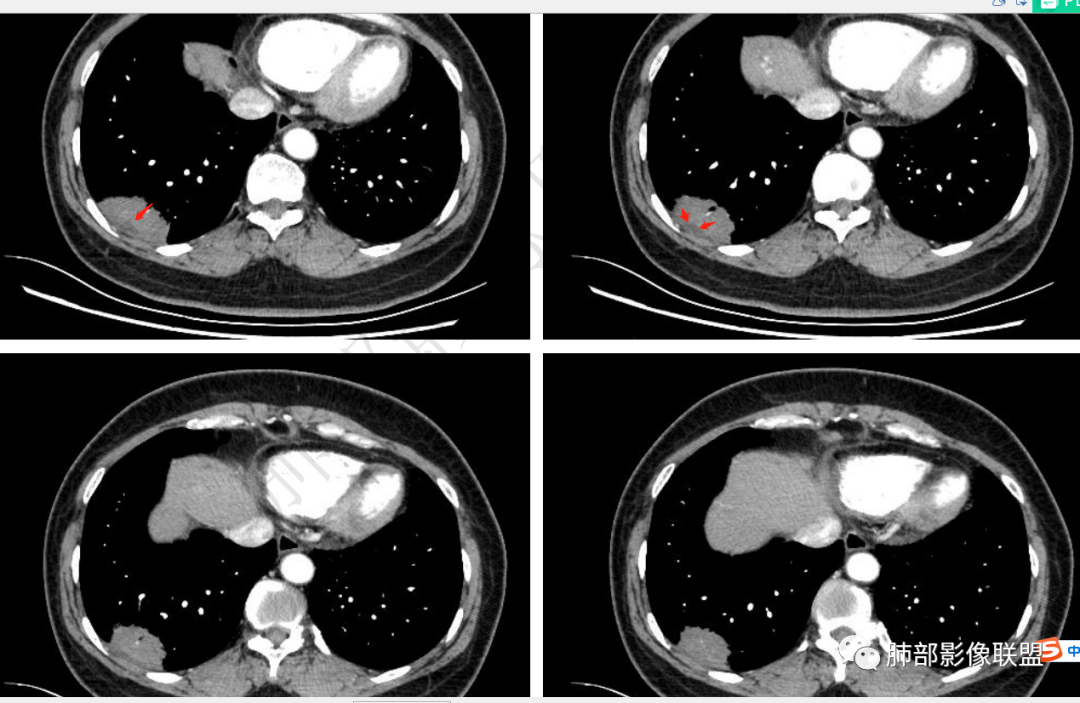

无症状体检发现右肺下叶不规则后基底段胸膜下实变影,整体边界清楚,部分有磨玻璃影,边界平直收缩,长轴平行胸膜,内部见支气管进入后截断,内部密度不均匀,增强扫描轻度不均匀强化,考虑炎性病变,隐球菌可能,鉴别腺癌

左肺下叶胸膜下团块影,长轴平行胸膜,边缘清晰,可见磨玻璃影,支气管进去后截断,胸膜糊墙,增强后轻度强化。考虑炎性肉芽肿病变,隐球可能。

右肺下叶胸膜下肿块,宽基底与胸膜相连,糊墙,边缘少许晕,局部边缘刀切,支气管进入后阻塞,强化均匀,考虑炎性病变,隐球菌可能,鉴别腺癌

体检发现右肺下叶胸膜下结节影,宽基底与胸膜相贴,边缘光滑,无分叶,毛刺,糊墙,周围见磨玻璃晕,支气管进入后阻塞,增强后轻度强化,内血管正常。首先考虑炎性,隐球?鉴别腺癌。

右肺下叶胸膜下病灶,长轴平行胸膜,支气管进入后堵塞,周边边界清楚,有少许周边磨玻璃影。强化可见内血管影,强化较均匀,无临床症状,考虑炎性病灶,肉芽肿性可能。